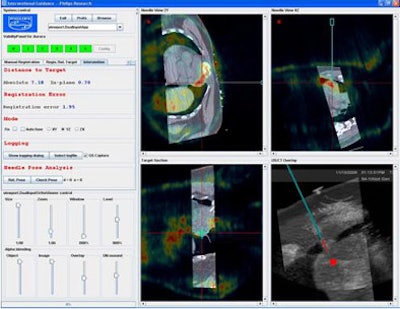

Finally, the researchers compared the results of different aiming methods with the tracking system versus conventional ultrasound/CT guidance. That is, two interventional radiologists did their best to aim the needles based on viewing CT/ultrasound images, versus aiming with the tracking system.

| Above, tracking angle for radiofrequency ablation of the lung based on CT/ultrasound guidance versus tracking method (below) yielded better results with automated tracking. |

Based on eight data points in six patients, and with a mean distance from the target of 78 ± 33 mm, the in-plane distance was 2.4 mm ± 1.2 mm with navigation compared to 14.4 mm ± 7.4 with conventional CT/US, and the difference in angles between the two methods was 10.5° ± 2.8°, Krücker said.

In two cases the researchers also successfully registered preprocedural CT scans with prior DICOM images. Registration with a prior MR scan was used for a renal radiofrequency ablation, and registration with a prior PET/CT scan was used to biopsy a lymphoma close to the heart, an organ that is critical to avoid during such procedures.

| Registration with a prior PET/CT scan was used to biopsy a lymphoma close to the heart. |

The results showed that the tracking system is accurate in the CT interventional suite with internal errors of around 3.8 mm, and the internal needle improves accuracy further to within 2.9 mm, Krücker said. The system improves needle aiming significantly as well, and provides target position information that would otherwise be unavailable, compared to only CT- or ultrasound-guided procedures, he said.